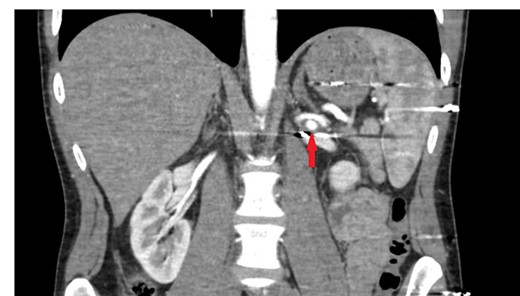

The patient was re-evaluated with CTA 3 weeks after discharge. Endovascular intervention was planned after observing that the left RAP was enlarged to 6 mm (Fig. 2). A renal angiogram was performed. After selectively catheterizing the left renal artery, a 6 × 3 mm filling extending inferiorly in the middle part of the left renal artery compatible with RAP was observed (Fig. 3). Following catheterization of the left renal artery with a long sheath, the lesion segment was passed with guide wire-catheter manipulations. Subsequently, a 6 × 22 mm covered stent (Advanta V12 Balloon Expandable Covered Stent, AMC, USA) was placed to include the RAP neck, and full expansion of the balloon and stent was achieved (Fig. 3). The control images revealed that the RAP was excluded from circulation, and the stent was patent. No embolism or bleeding was observed in the distal renal artery branches.

The filling image of the left renal pseudoaneurysm and the inserted covered stent.